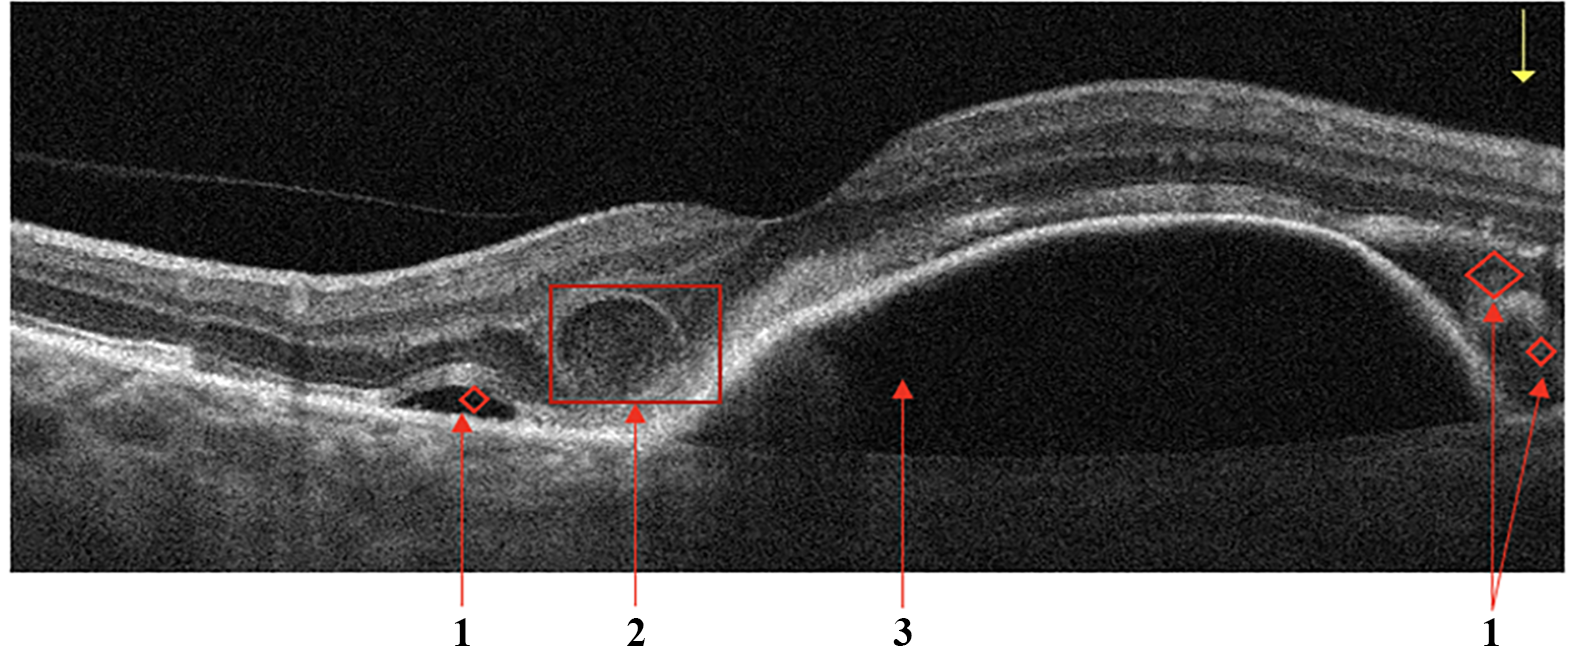

Retinal Vein Occlusion

Secondary ME is the leading cause of visual loss in patients with central retinal vein occlusion (CRVO). OCT is the critical imaging modality to diagnose and formulate a treatment plan for cystic macular edema (CME) of this etiology. In contrast to DME, the ME secondary to a branch or CRVO is generally cystic and localized to the inner retina following leakage from engorged veins, Fig.5a. OCT scans also show a higher level of hyperreflectivity of the inner retina due to ischemia. The long-term prognosis of vein occlusion will depend on the degree of ischaemic damage to the retinal tissue and the structural damage to the neural pathways after CME resorption. The presence and severity of any DRIL is an indicator of likely visual prognosis [35, 36].

Figure 5: Retinal Vein Occlusion (RVO). Cystic macular edema in central retinal vein thrombosis. (a): 1 - Intraretinal fluid (IRF), 2 - hyperreflectivity of the inner retinal layers; Signs of Retinal Artery Occlusion (RAO) (a): 1 - Increased hyperreflectivity of the inner retina following ischemia, 2 - prominent middle limiting membrane (p-MLM).

Retinal Artery Occlusion

Occlusion of the central retinal artery (CRAO) and its branches (BRAO) leads to the formation of acute tissue ischemia, giving a specific OCT picture - pronounced hyperreflectivity, loss of homogeneity, and edema of the inner parts of the retina containing the ganglion cells, Fig.5b. Also, a biomarker of acute ischemia is a prominent middle limiting membrane (p-MLM) - a hyperreflective line or band located in the inner part of the outer plexiform layer at the border with the outer nuclear layer. It is not ordinarily visible, which appears in the early period of the pathological damage and is due to opacification of the middle retinal layers [37].

Vitreomacular Interface Disease

VID is a term used to describe a group of diseases resulting from the pathologic course of the normal age-associated process of a posterior vitreous detachment. Usually, the process is completed without retinal deformation. However, vitreo-retinal traction occurs in cases of adhesion between the retina and vitreous body, which can lead to macular tears, cysts, or holes developing [38].

• When pathologic adhesion of the posterior hyaloid to the retinal interface forms, progressive posterior vitreous detachment causes axial traction of the inner limiting membrane, formed by Müller cell end feet that deforms the retinal tissue, Fig.6a.

• Macular retinal hole is a complete defect in the inner layers of the retina that extends to the RPE, Fig.6b. IRF appears as different-sized cavities with hyporeflective contents. In macular retinal tears, the intraretinal fluid is contained within the borders of the tear [39].

• One of the variants of MH with preservation of the integrity of the photoreceptor layer is a lamellar tear of the neurosensory retina, Fig.6c. The condition is often asymptomatic and requires no treatment, but regular monitoring by a medical retina specialist is advised.

Figure 6: Vitreomacular Interface Disease (VID). Vitreomacular traction syndrome (a): 1 - Posterior hyaloid membrane, 2 - Vitreomacular adhesion zone, 3 - Emerging neurosensory retinal defect; Retinal interface disorder (b): 1 - intraretinal fluid (IRF), 2 - Edges of the tear, 3 - detached posterior hyaloid membrane; Lamellar tear (c).